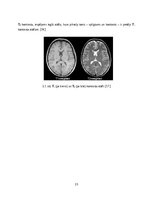

Magnētiskās rezonanses tomogrāfs sastāv no daudziem komponentiem, kas saskaņoti darbojas vienotā sistēmā, lai iegūtu ķermeņa audu šķērsgriezumu divdimensionālus attēlus. Iegūtos attēlus izmanto orgānu morfoloģisko struktūru izmaiņu diagnosticēšanai. Tāpat no tiem iespējams konstruēt trīsdimensionālus anatomisko struktūru modeļus. Procedūras laikā netiek izmantots jonizējošais starojums, tādēļ tā nav kaitīga pacienta veselībai.